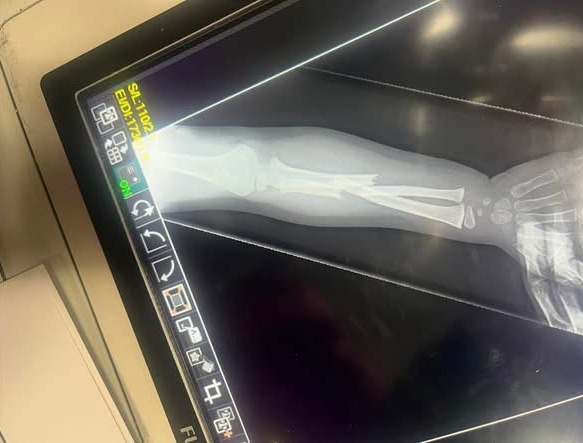

Her daughter’s arm was broken. In two places. And according to the doctor, it was not an accident. The breaks were consistent with the arm being stepped on or slammed in a door.

A child’s arm was broken. Twice. In one day.